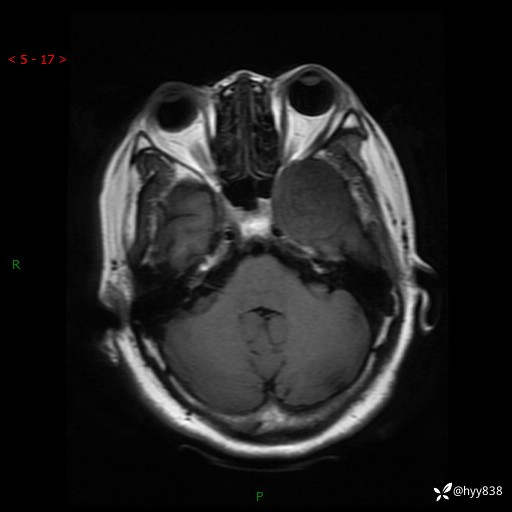

现病史:患者于1个月前无明显诱因出现左眼视力下降,无头痛,无恶心、呕吐,无肢体活动障碍,无意识障碍等伴随症状,后就诊于监利市人民医院行眼眶MRI检查提示“左侧中颅窝底占位性病变”,今日为求进一步诊治前来我院,门诊以“颅内占位性病变”收入院。 发病以来,患者精神、饮食及睡眠良好,大、小便正常。

颅脑MRI平扫+增强